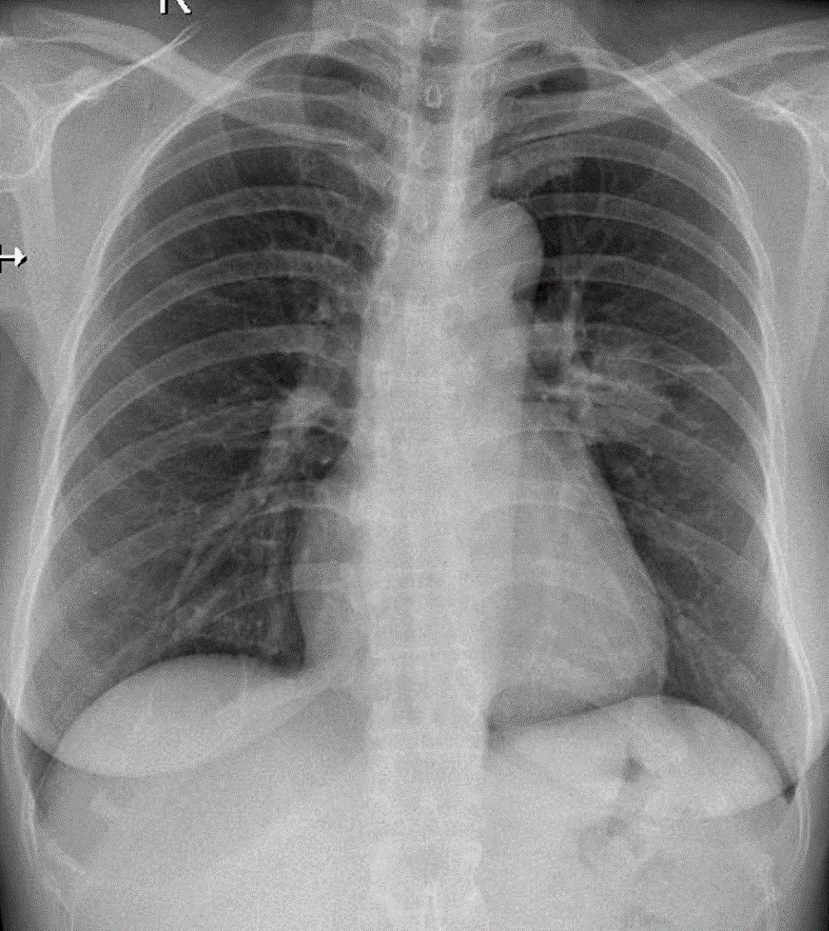

1-U rốn phổi (T) 2-Đóng vôi sụn sườn trước hai bên